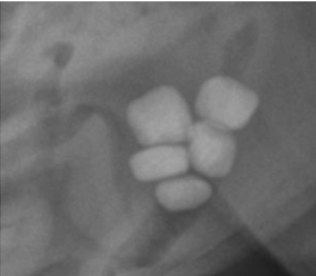

12

Q

What urolith is this an example of?

A

Calcium oxalate - irregular appearance